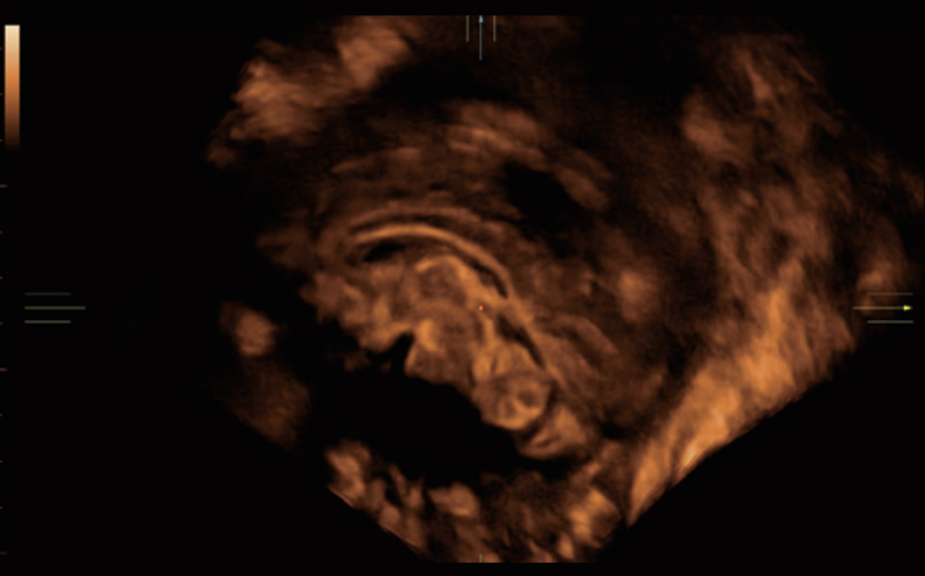

Nuewa I9? ??? ???? ?? ??? ?? ??? ???? ?? ??? ???? ???? ??? ?????. ??? ??? ??? ?? ????? ?? ???? ???? ???? ???? ??? ???? ??? ??? ???? ??? ???? ??? ?? ?????.